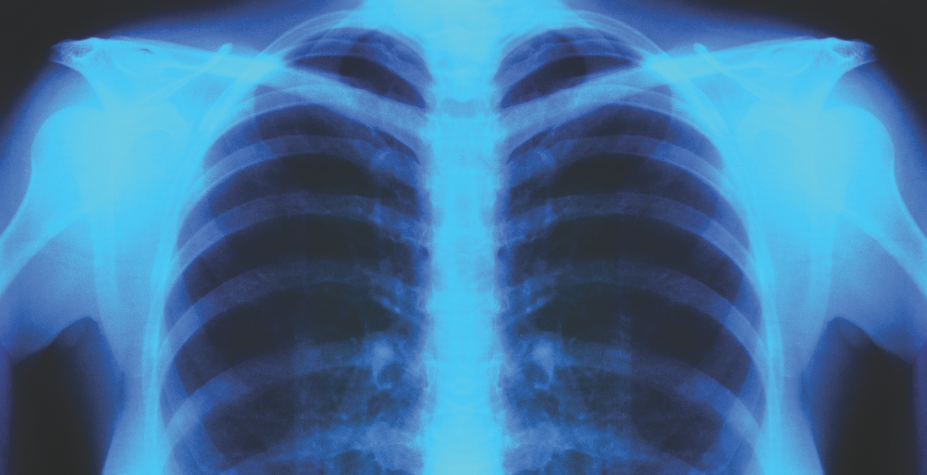

Bisrat Haile, MD; Orlando Carpio, MD; Sameh Abdelaal, MD; Rafael Ilyayev, MD; Rajat Mukherji, MD

A 73-year-old female, nursing home resident, with a past medical history of dementia and breast cancer, was found to have a significant weight loss over a period of 5 months associated with poor appetite. ...